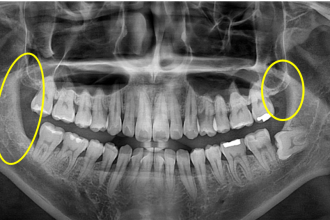

사랑니발치

굿프렌즈 치과 임상 케이스